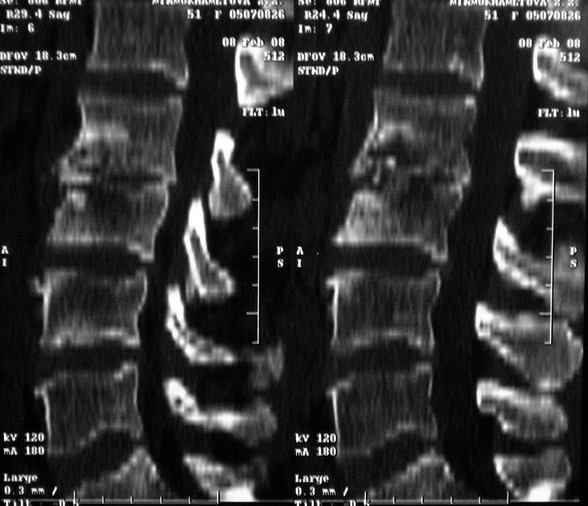

MRI через три недели

|

По данным представленных КТ и МРТ у больной имеется достаточно выраженная степень деструкции тел позвонков (около 30% общей костной массы тела позвонка), что определяет высокий риск возникновения патогических переломов и появления локальной кифотической деформации на этом уровне.

По-поводу последних изменений в клинике - это не миелопатия, а симптом прилипшей пятки из-за вовлечения в процесс псоаса - формируется натечник. Поэтому УЗИ контроль паравертебральных тканей.

Данные МРТ выкладываешь некорректно - это не "контроль в динамике", а поход по Сусанинским местам, сравниваемые срезы за разные даты должны быть одинаковыми.